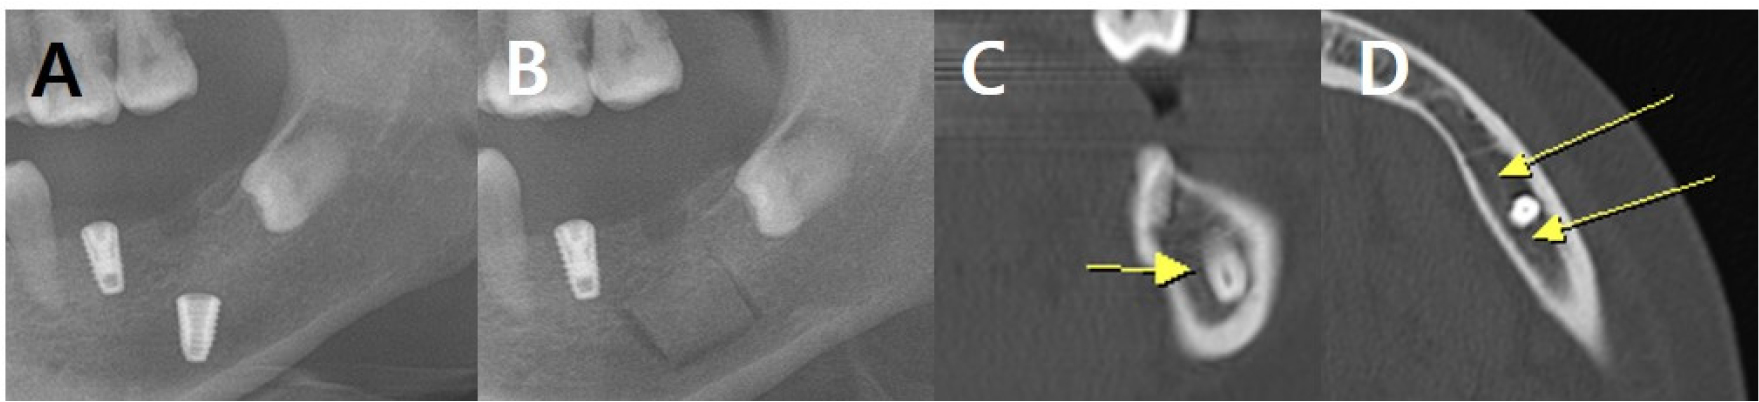

Fig. 5.

Radiographic findings in case 2 at the first visit. (A) Panoramic radiograph shows the implant in the left mandible, (B) Panoramic view showing the outline of the bony window for implant removal, (C and D) Coronal and axial CT images showing that the fixture in the #37 region is inserted almost to the lower margin of the inferior alveolar canal. The inferior alveolar canal runs biased to the lingual side, and it seems to be slightly invaded by the fixture, but it seems to be pushed to the lingual side (Yellow arrows indicate the buccal cortex of the inferior alveolar canal).

A 52-year-old woman was referred for the removal of an implant fixture in the #37 region that intruded into the mandible during implant surgery. The patient had a grade 2 intellectual disability, and the above event occurred because of a lack of cooperation during surgery. While adjusting the vertical depth using a hand wrench, the patient accidentally closed her mouth. Therefore, the implant fixture sank into the mandible. Sinking of the implant fixture in the left mandible was confirmed using CT (Fig. 5).